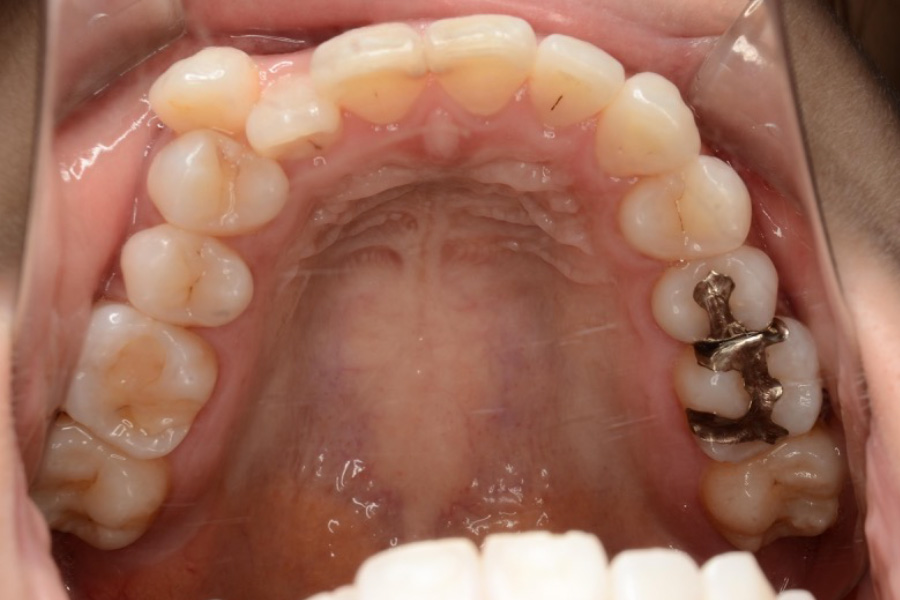

【20代女性】

八重歯、下の歯のガタつきを

インビザライン矯正で治療したケース

治療後

主訴 八重歯、下の歯のガタつきが気になる

治療内容 インビザライン矯正

小臼歯抜歯